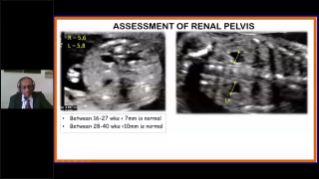

L'ottimizzazione dei flussi di lavoro in ambito ostetrico e ginecologico ├© necessaria per completare grandi volumi di visite di screening per la salute delle donne. Ad esempio, le malformazioni del sistema nervoso centrale (SNC) sono una delle anomalie congenite pi├╣ comuni. A causa di varie circostanze che limitano l'accuratezza delle immagini, come la posizione poco adeguata del feto, l'MSP ├© particolarmente difficile da rilevare tramite l'ecografia 2D. Pertanto, il rilevamento e le misurazioni automatizzate possono migliorare notevolmente l'efficienza della scansione.